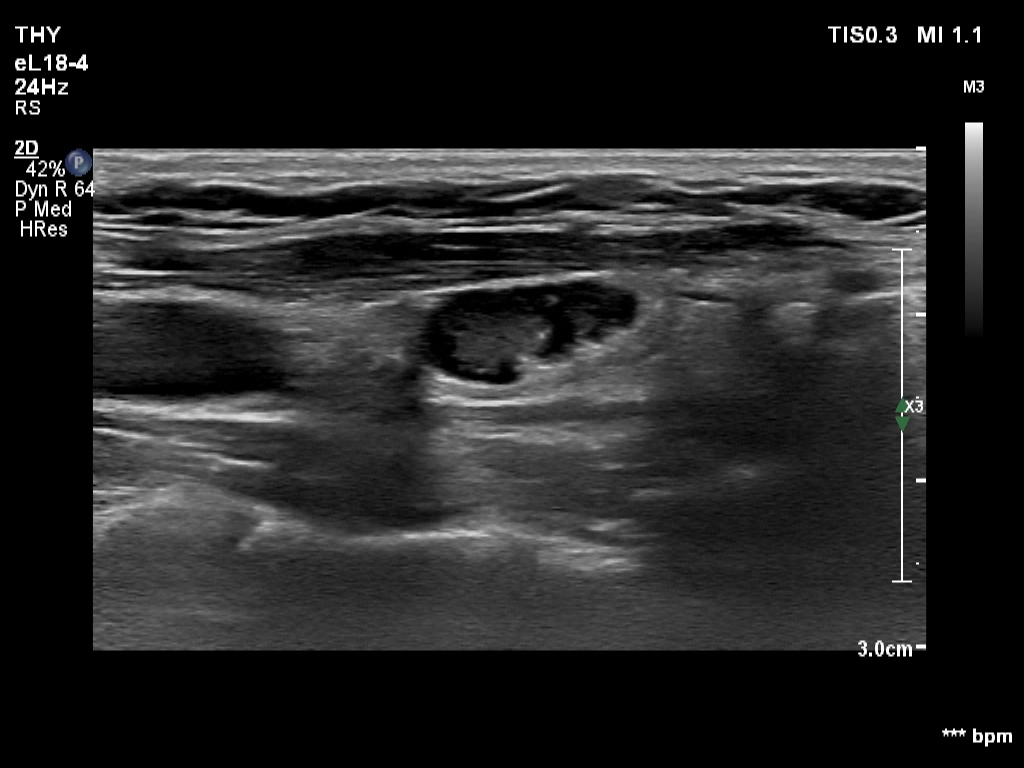

Right lobe, longitudinal scan

Left lobe, another longitudinal scan - with better harmonization. Great proportion of the node seems to be deceptively cystic.